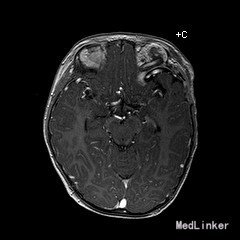

2岁9月患儿,因“左眼睑下垂1年余,头痛、呕吐8天”入院。家属1年前发现患儿左侧眼睑下垂,无法自行张开,一直未予特殊诊治。8天前患者哭闹频繁,诉头痛如爆炸样,剧烈难忍,并出现呕吐胃内容物数次,无伴抽搐、视力下降,无意识障碍。当地医院头颅MRI提示:左侧眼眶扩大,左侧眼球外上方泪腺区见一条状迂曲异常信号影,T1WI呈等信号,T2WI上病灶外缘呈高信号,内为等信号,增强扫描病灶中央呈条状明显强化影,边缘无明显强化,双侧大脑半球对称,灰白质对比正常,未见局灶性信号异常,左侧中颅窝前分蛛网膜下腔增宽,内为脑脊液信号;各脑室、脑池大小、形态均正常,中线结构居中,幕下小脑、脑干无异常,矢状面示垂体大小形态正常,未见局灶性信号异常;增强扫描未见明显异常强化。

患儿术后2周左眼睑下垂较术前好转。双侧瞳孔反射、眼球活动均无异常。 丛状神经纤维瘤主要发生于眼睑,在出生后或幼年时期即出现症状和体征。侵袭范围广泛,包括眼睑、眶内软组织、眶骨和邻近的脑、颞部等。眼部最早和最多见为上、下睑软性肥厚,皮下瘤组织增生,使上、下睑隆起。眼睑皮肤常有淡棕色色素斑,眼球向前突出和向下移位。眼球突出虽然很显著,但向眶内纳入并不困难。肿瘤组织可直接侵袭眶内各种结构,上睑提肌首先被波及,引起上睑下垂,上举不足或不能。MRI可准确显示病变的范围尤其显示病变与邻近结构的关系,也可清楚显示其他部位伴发的肿瘤,但难以清晰显示眶壁骨质改变。手术治疗是必要的,手术切除应注意以下问题:1.眼睑病变的切除;2.眶内病变的处理;3.提上睑肌的处理;4.眶骨缺失的处理。丛状型术前诊断容易,但治疗较为棘手,易复发。